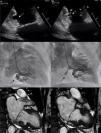

A 77-year-old female with past medical history of diabetes, dyslipidemia and atrial fibrillation presented to our service complaining of shortness of breath. She was previously treated with metoprolol, rivaroxaban and furosemide. Physical exam showed no jugular venous distention, heart auscultation highlighted a holosystolic murmur at the mitral area radiating to the axillary region, presented lower extremity edema, rest was normal. Transthoracic echocardiogram showed no contractility defects, basal hypertrophy was noted with a myocardial crypt at the inferior basal region (Fig. 1A,B, white arrow; video 1 of the supplementary data); left ventricular ejection fraction was preserved with both severe mitral and tricuspid regurgitation. Coronary angiogram did not reveal coronary artery disease, and left ventriculography showed a “2-finger shaped” image at the inferior basal region with contrast penetration between them (Fig. 1C,D; video 2 of the supplementary data). Cardiac magnetic resonance confirmed the diagnosis of myocardial cleft (Fig. 1E,F, black arrow), commonly seen as a rare congenital anomaly in patients with hypertrophic cardiomyopathy. The heart team decided to perform a bioprosthetic mitral valve replacement with tricuspid annuloplasty.